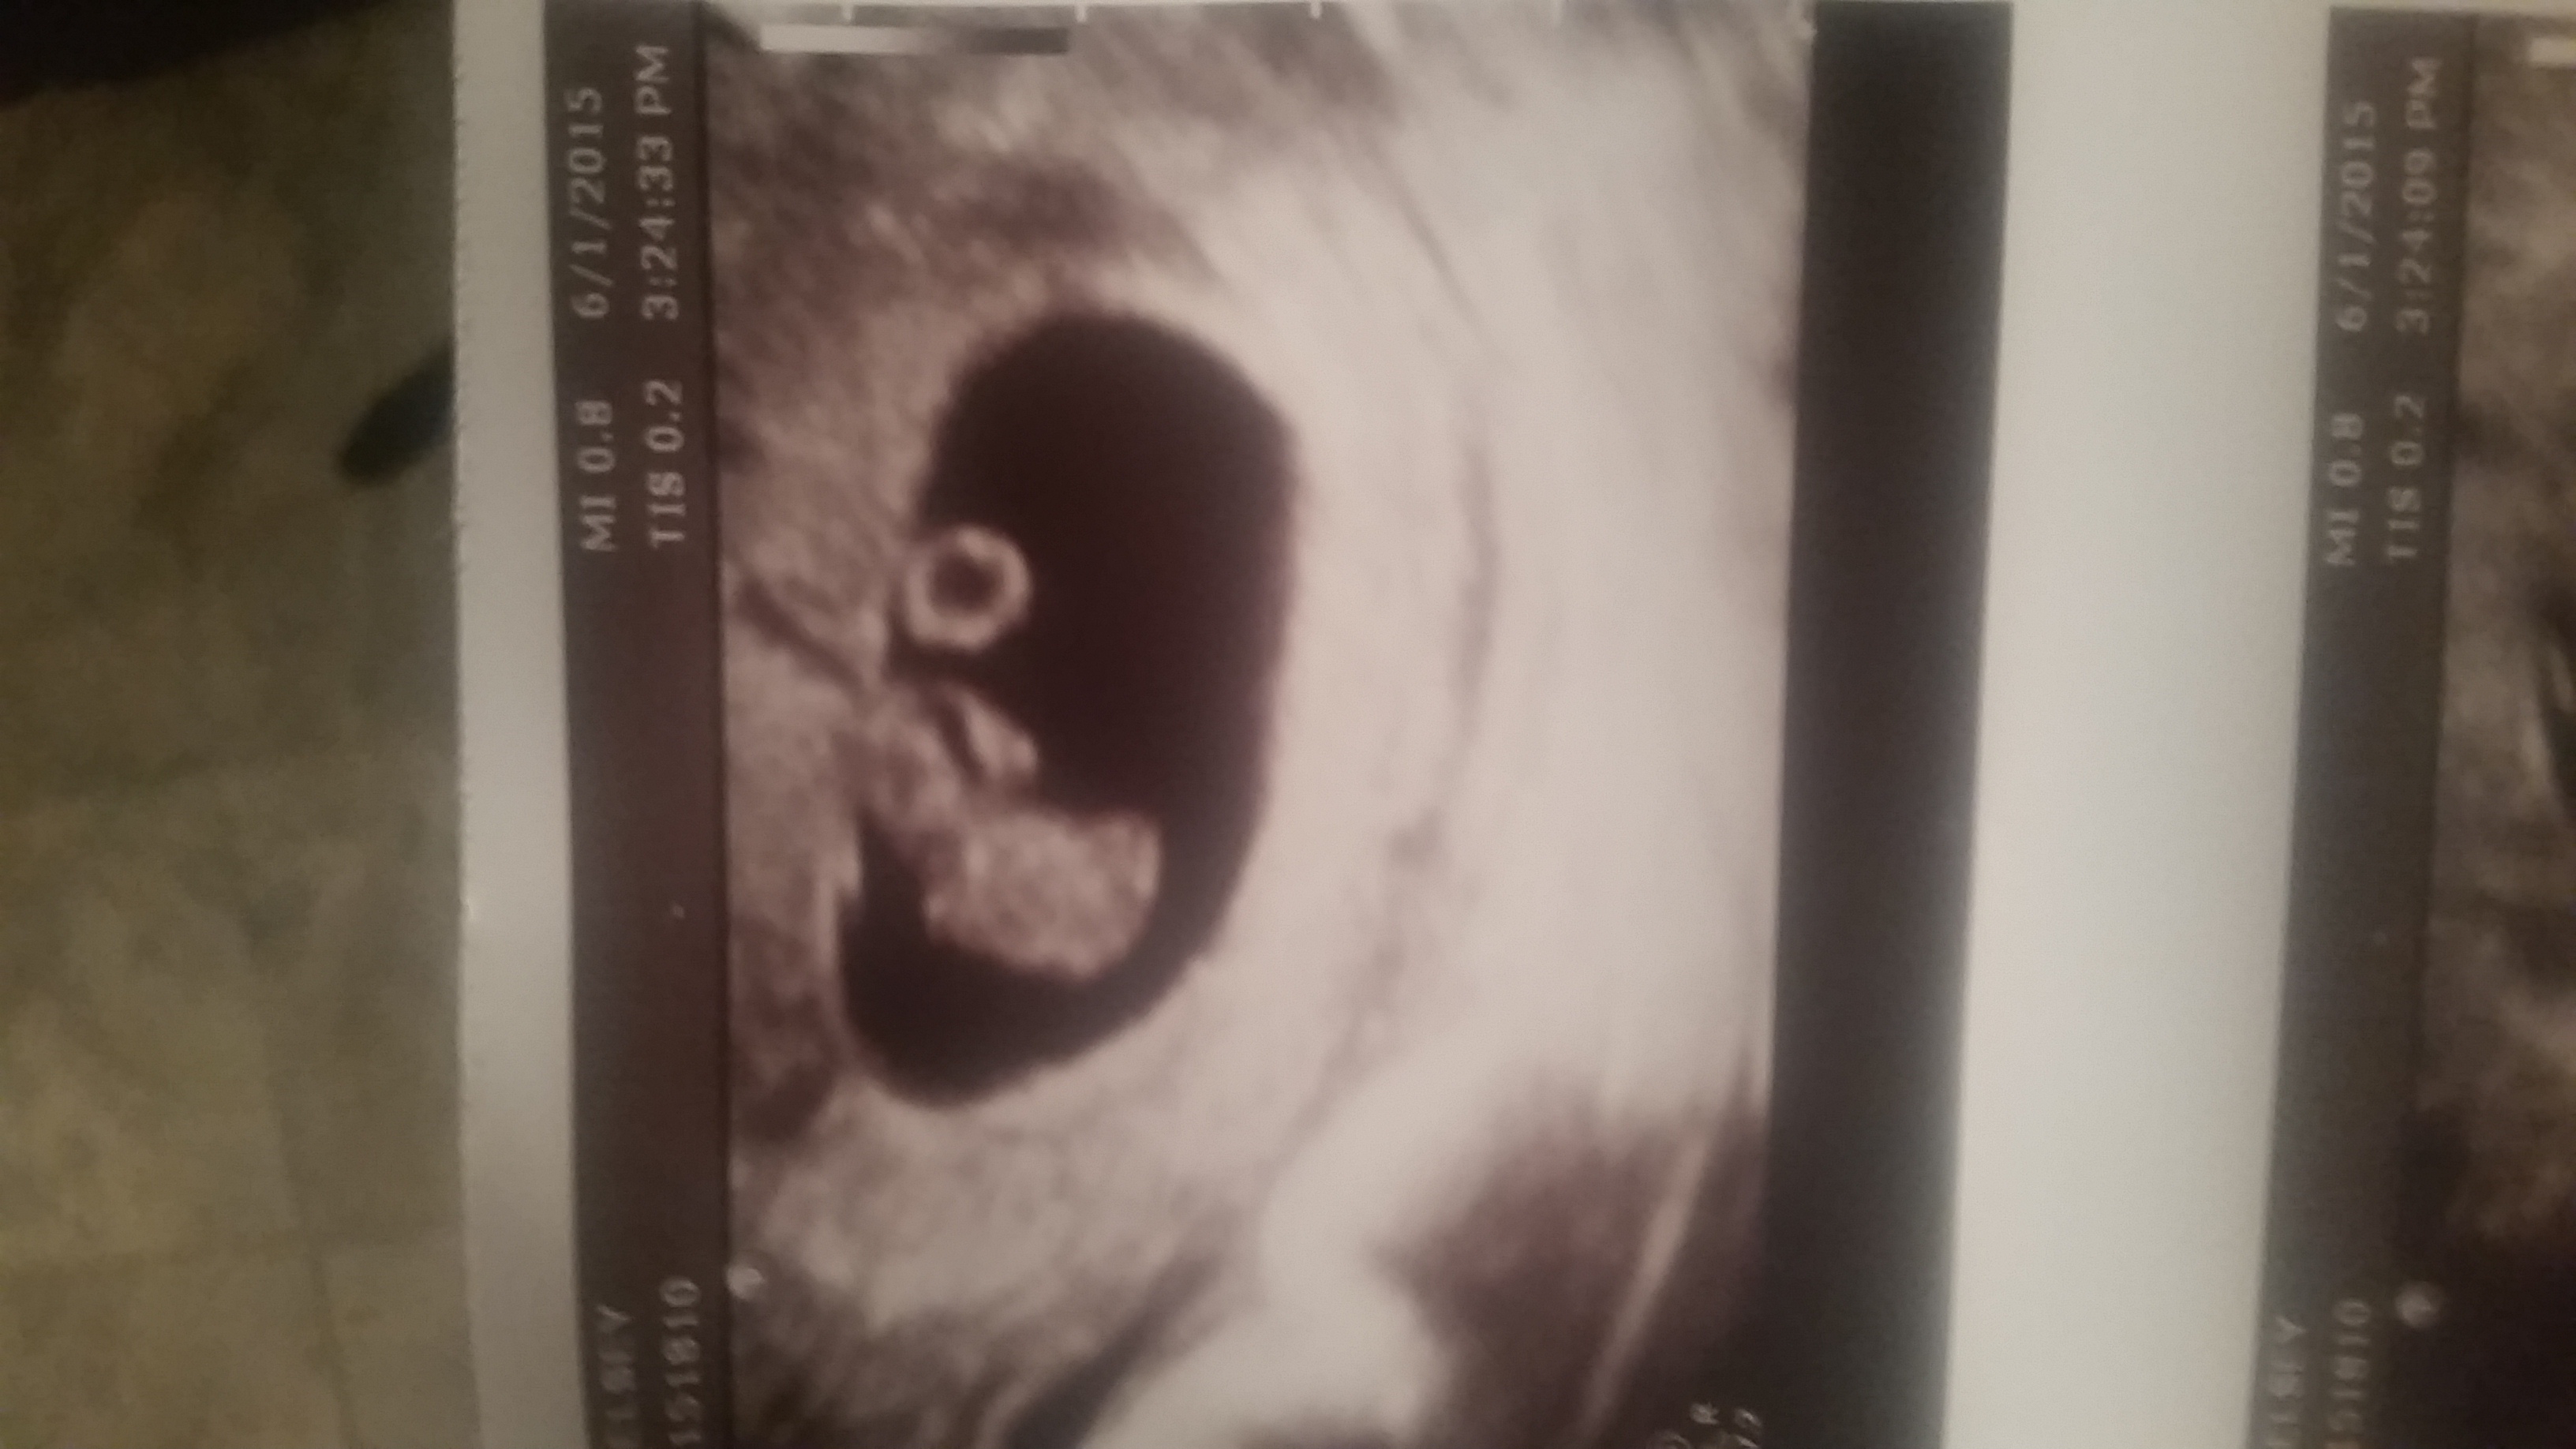

Mine was correct, baby was on the right side of the 6w4d transvaginal ultrasound and I'm having a boy. But the odds are 50/50, so it's not really much of a gamble.

Transvaginal:

Left - girl

Right - boy